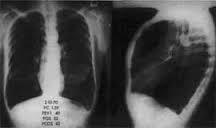

COPD Chest Xray COPD Chest XRAY 1. flat diaphragm 2. tear shaped heart 3. Increase AP/ retrosternal airspace *Emphysema: pruning of pulmonary vessels and bullae*